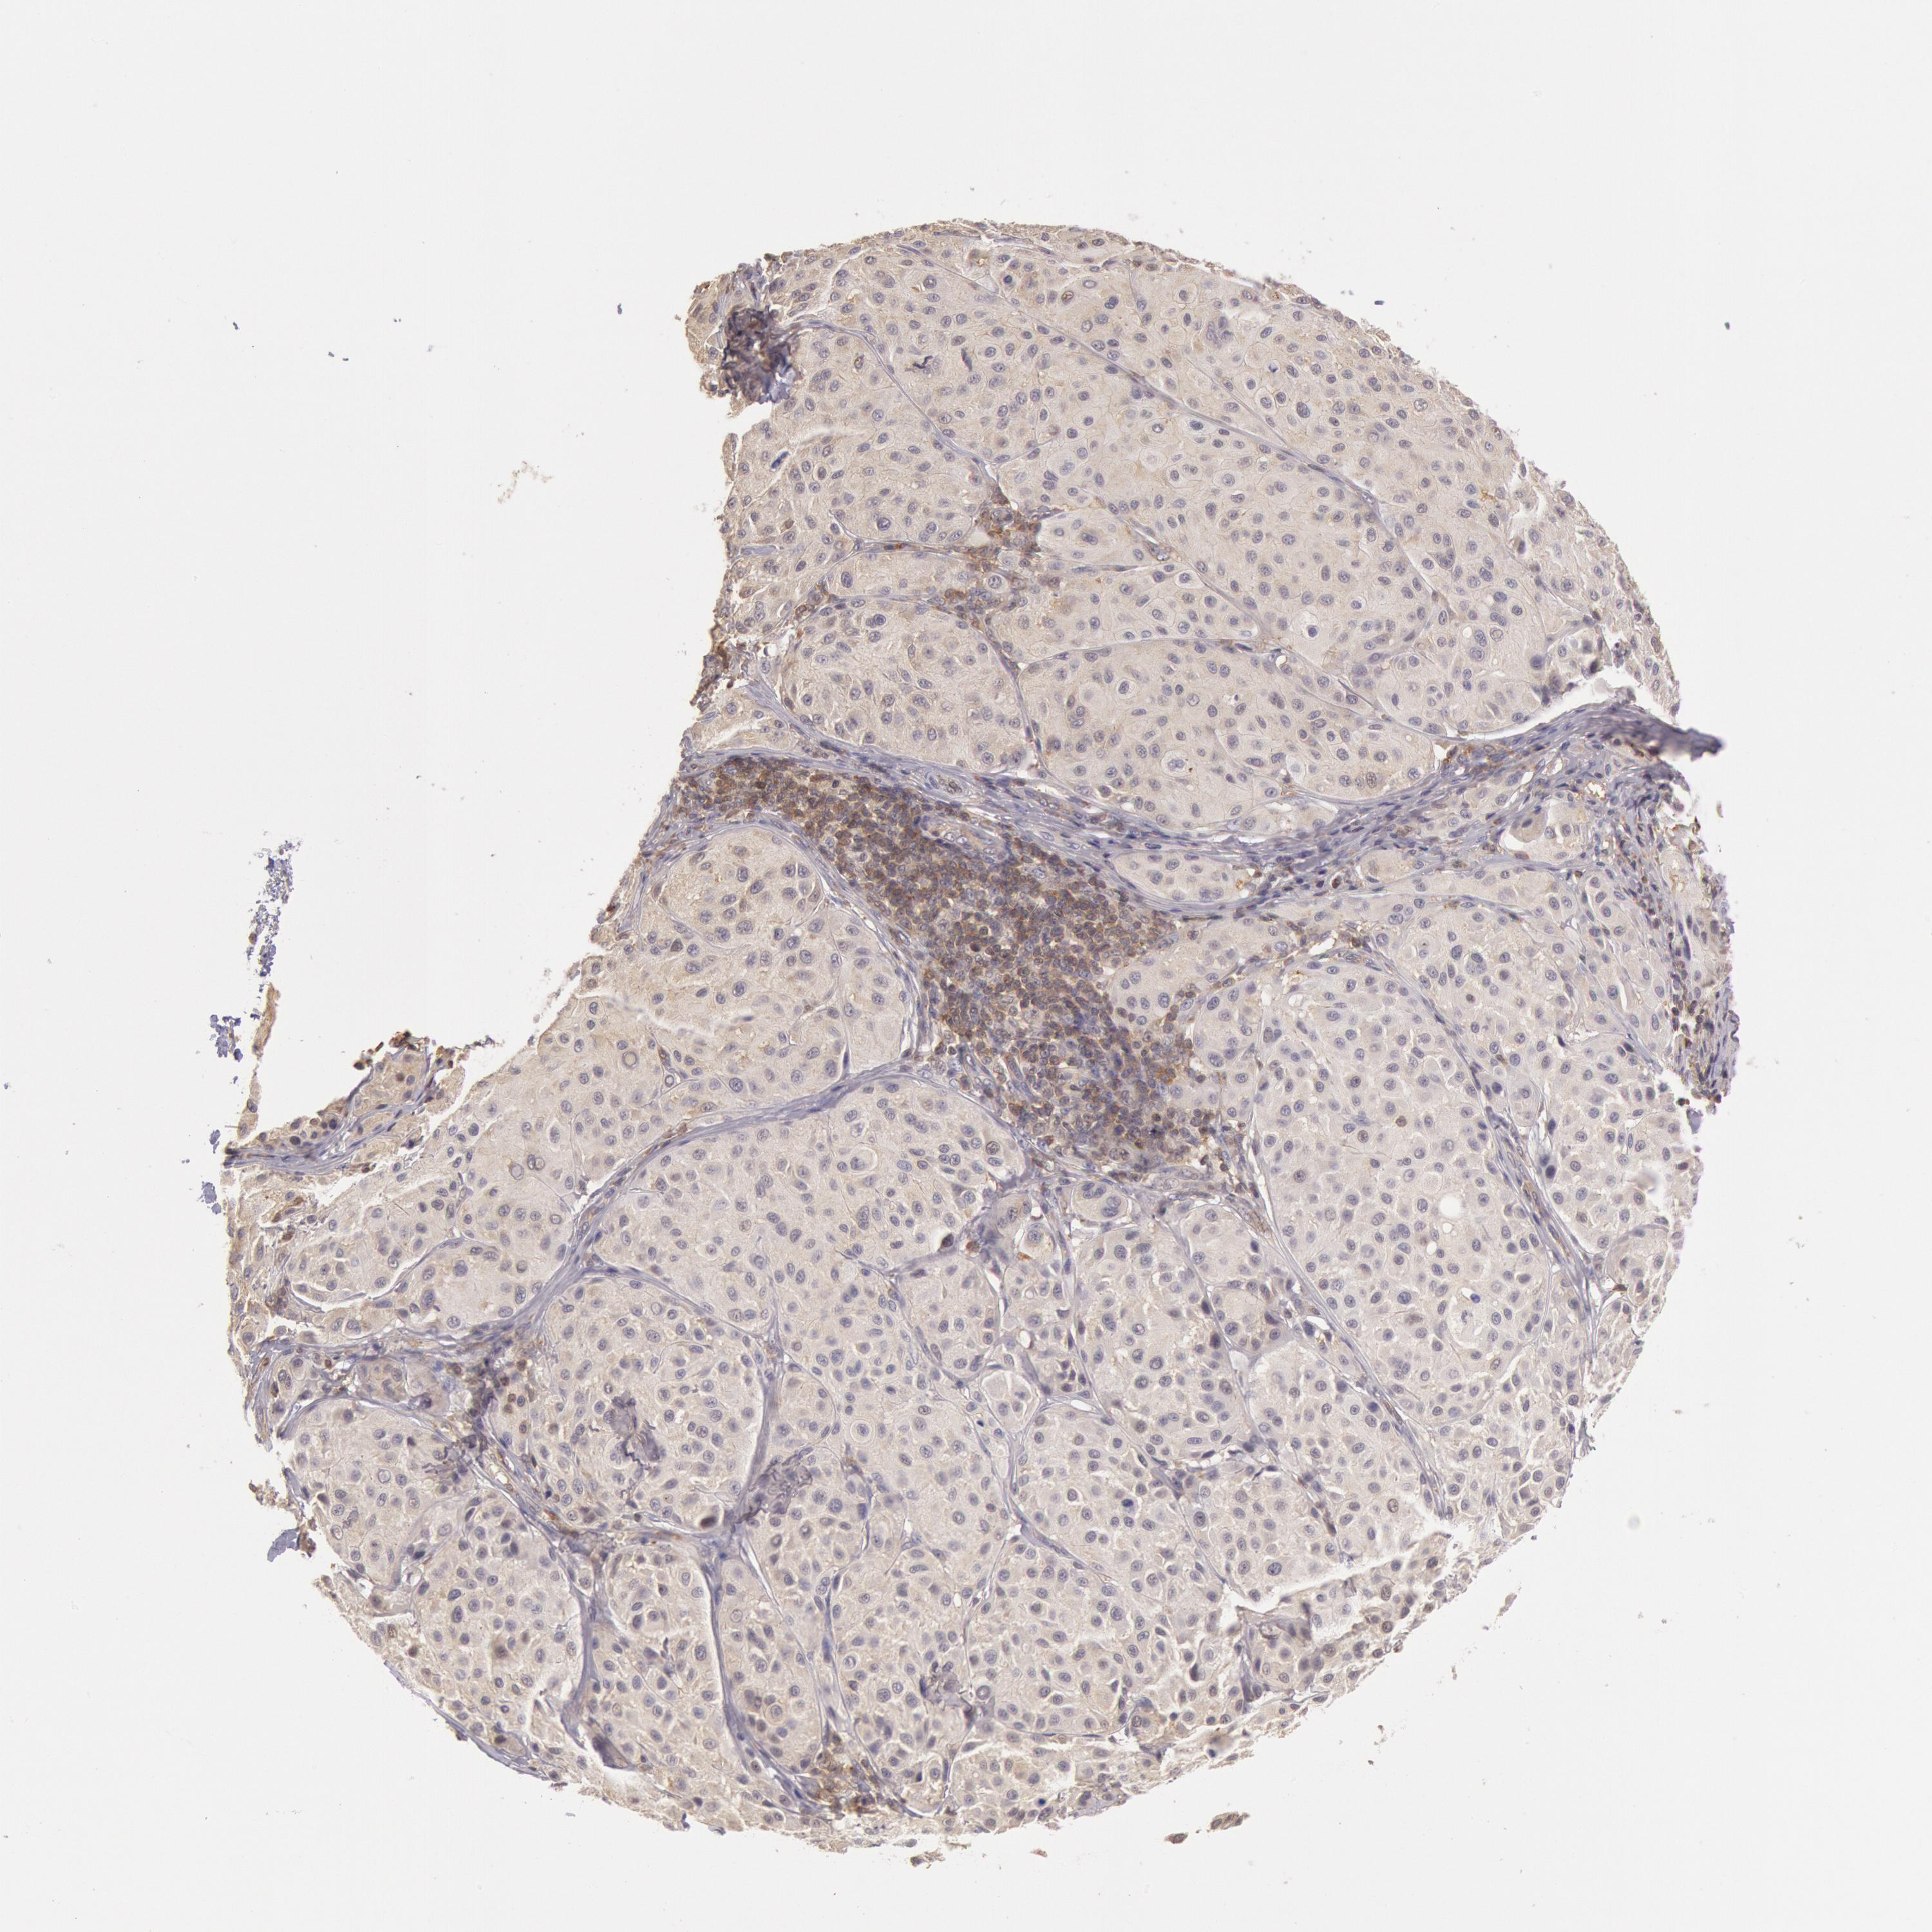

MELANOMA - Protein expressioni

A mouse-over function shows sample information and annotation data. Click on an image to view it in a full screen mode. Samples can be filtered based on level of antibody staining by selecting one or several of the following categories: high, medium, low and not detected. The assay and annotation is described here.

Note that samples used for immunohistochemistry by the Human Protein Atlas do not correspond to samples in the TCGA dataset.

Antibody stainingi

Antibody staining in the annotated cell types in the current human tissue is reported as not detected, low, medium, or high, based on conventional immunohistochemistry profiling in selected tissues. This score is based on the combination of the staining intensity and fraction of stained cells.

Each image is clickable and will lead to virtual microscopy that enables deeper exploration of all samples and also displays staining intensity scores, fraction scores and subcellular localization as well as patient and tissue information for each sample.

Antibody HPA001275

Antibody CAB017442

Staining

High

Medium

Low

Not detected

Intensity

Strong

Moderate

Weak

Negative

Quantity

>75%

75%-25%

<25%

None

Location

Nuclear

Cytoplasmic/membranous

Cytoplasmic/membranous,nuclear

Malignant melanoma, NOS

Malignant melanoma, Metastatic site